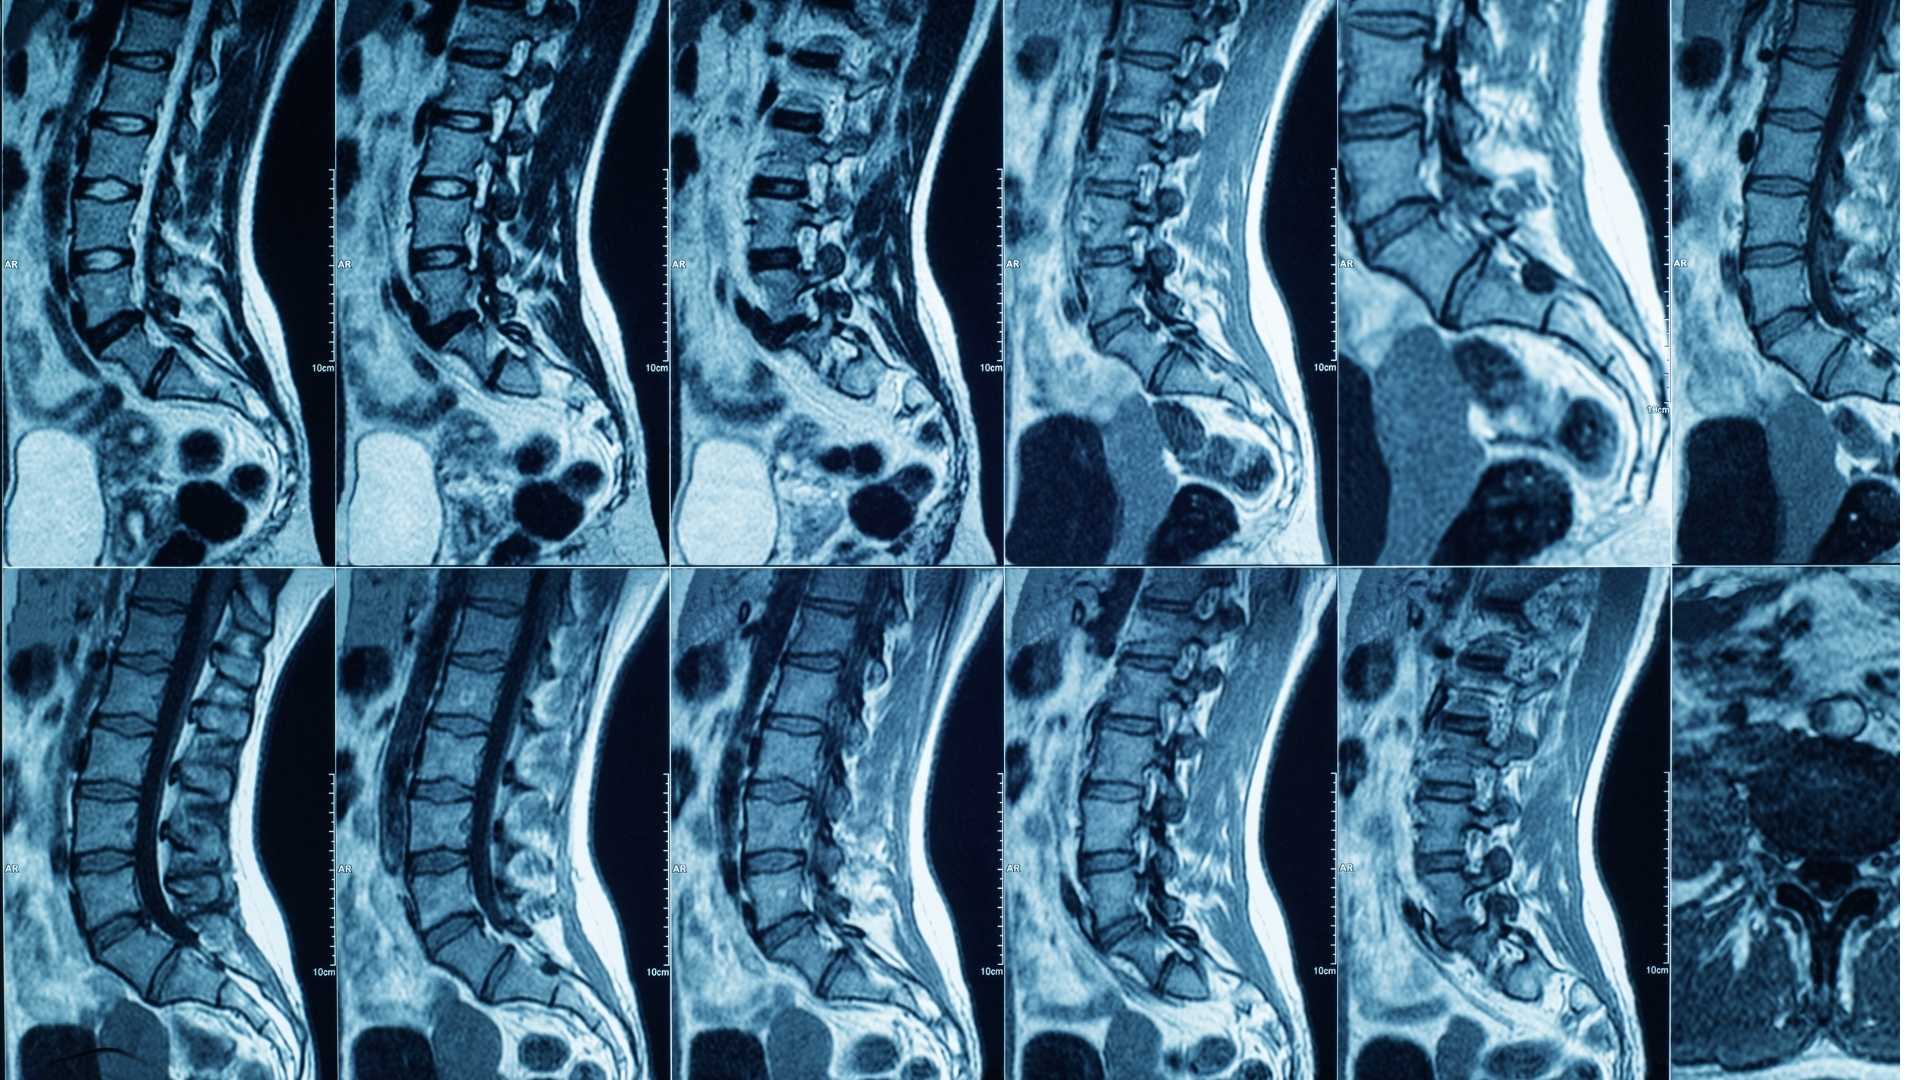

A Magnetic Resonance Imaging (MRI) scan is a medical imaging procedure that uses a strong magnetic field and pulses of radio waves to produce detailed images of the inside of your body. To get an MRI scan, the patient lies on a table that is slid inside a large cylindrical magnet. The magnet creates a strong magnetic field to align the hydrogen atoms in water molecules throughout your body. Radio waves are then sent through the patient’s body.

The magnetic field causes the water in your body to resonate at a frequency that depends on the amount of hydrogen it contains. This resonance is then picked up by a sensor that records the information and turns it into a 3D image. These MRI scanners use a solid electromagnet to create a magnetic field, whereas CT scanners use an X-ray machine.